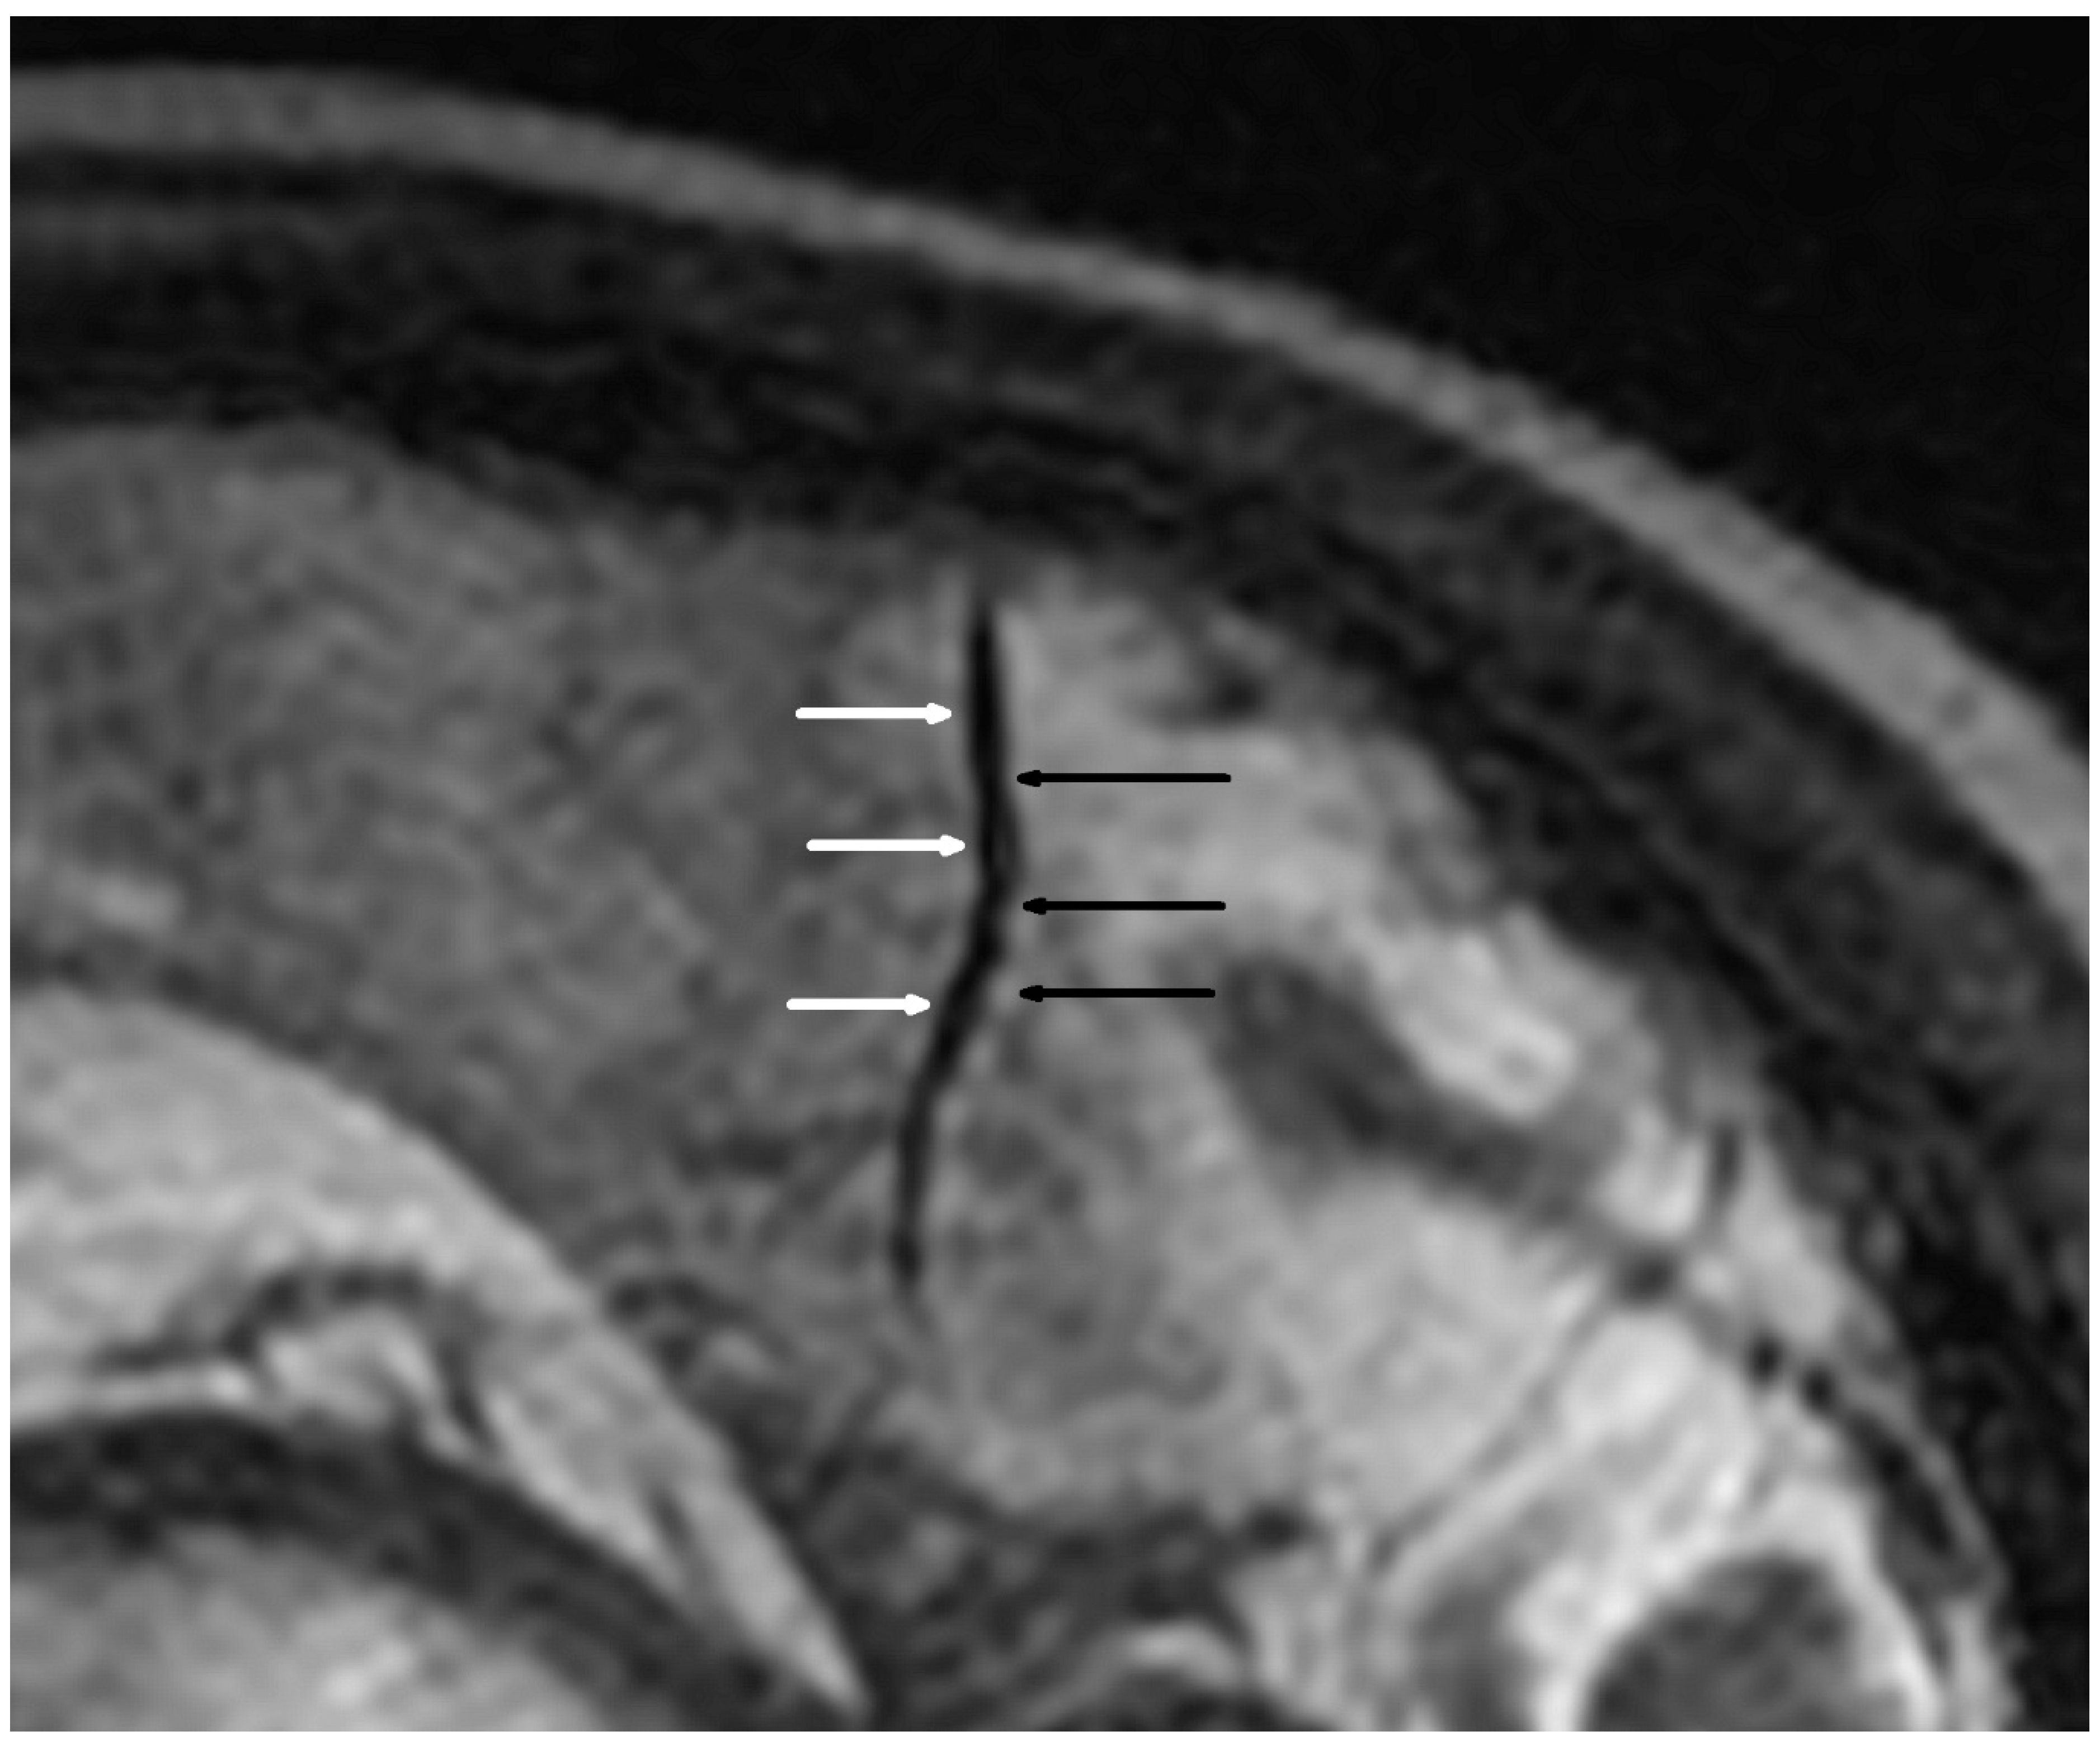

3.1. Vascular Alterations

| Alternating narrowing and dilatation in secondary vascular branches | 13/38 (34.2) | 1/38 (2.6) | <0.001 |

| Alternating narrowing and dilatation in tertiary vascular branches | 13/38 (34.2) | 1/38 (2.6) | <0.001 |

| Alternating narrowing and dilatation in secondary and tertiary vascular branches | 16/38 (42.1) | 2/38 (5.3) | <0.001 |